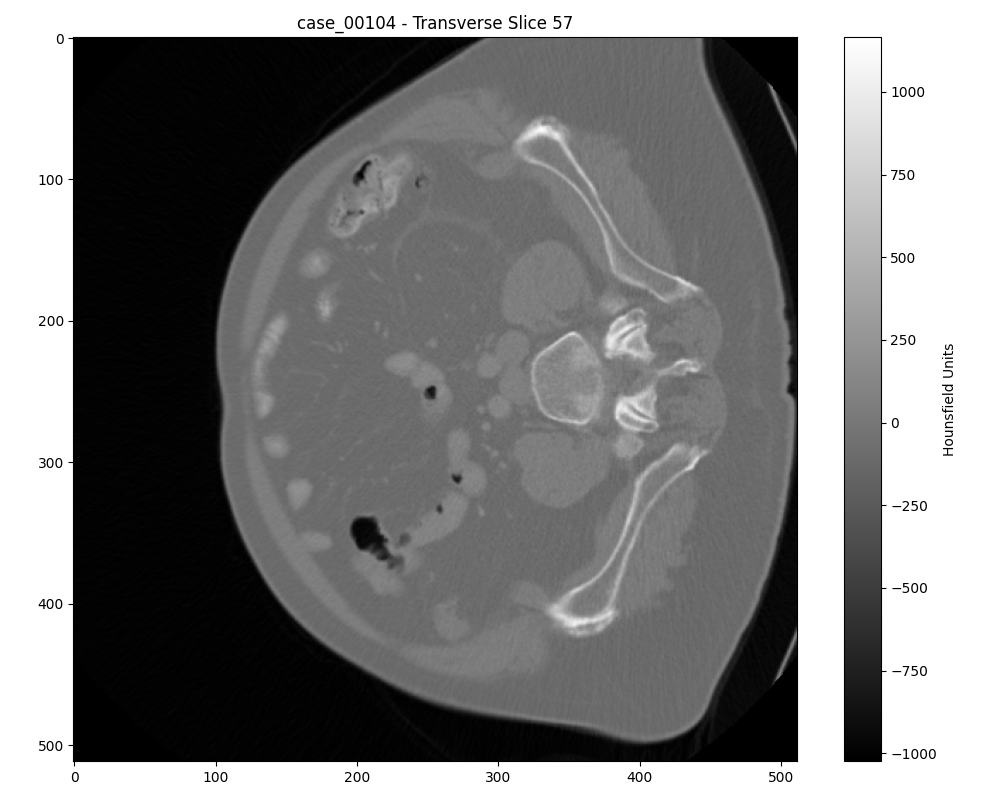

Axial slice of a malignant tumor

Axial slice of a benign tumor

Another axial slice of a benign tumor

Case 00104: Advanced malignant tumor with 3D volume visualization (top) and optimal 2D slice selection (bottom)

Additional Case Study: Malignant Tumor

Case 00082: Early-stage benign tumor with 3D volume visualization (top) and optimal 2D slice selection (bottom)

Additional Case Study: Benign Tumor